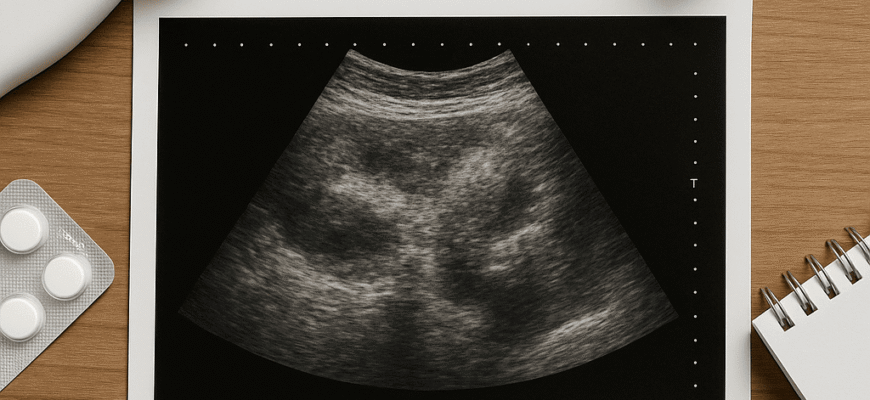

- УЗД

І діагностування. Чесно, не все так просто. Часто потрібні додаткові обстеження. УЗД — як перша зустріч, як відкриття дверей до світу підшлункової залози. Комп’ютерна томографія (КТ) — детальний погляд, що проникає глибше. Магнітно-резонансна томографія (МРТ) — наче віртуальна подорож організмом.

Всі ці методи допомагають з’ясувати, що видозмінилося: чи звичайні ці структурні зміни підшлункової залози чи… підлість, яку треба лікувати.